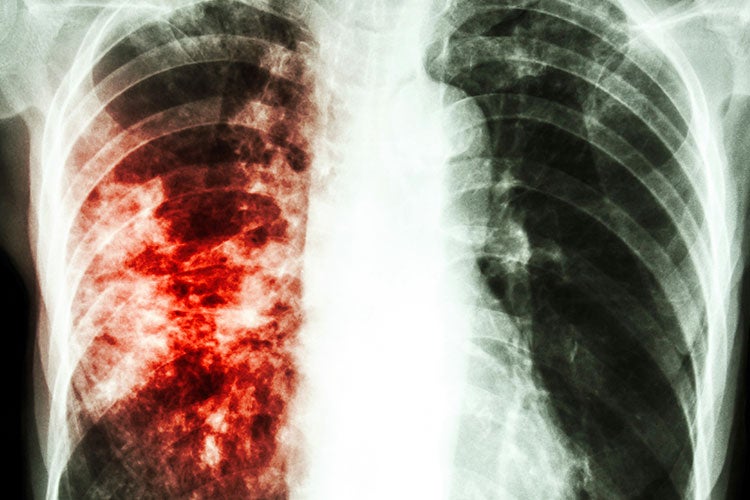

Симптомы и признаки туберкулеза: как распознать заболевание

Раздел: Визуальные уроки